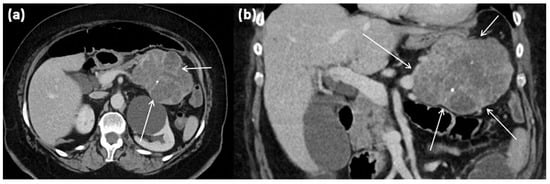

Figure 16.

MRI of a 60-year-old patient with a partly cystic and partly solid mass of the pancreatic tail. Arterial T1w after gadolinium-based contrast administration (a) typical peripheral hyperarterilization (arrows) can be seen. In T2w, solid as well as cystic parts are present (b).